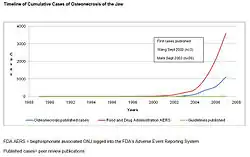

The first three reported cases of bisphosphonate-associated osteonecrosis of the jaw were spontaneously reported to the FDA by an oral surgeon in 2002, with the toxicity being described as a potentially late toxicity of chemotherapy.[12] In 2003 and 2004, three oral surgeons independently reported to the FDA information on 104 cancer patients with bisphosphonate-associated osteonecrosis of the jaw seen in their referral practices in California, Florida, and New York.[13][14][15] These case series were published as peer-reviewed articles – two in the Journal of Oral and Maxillofacial Surgery and one in the Journal of Clinical Oncology. Subsequently, numerous instances of persons with this adverse drug reaction were reported to the manufacturers and to the FDA. By December 2006, 3607 cases of people with this ADR had been reported to the FDA and 2227 cases had been reported to the manufacturer of intravenous bisphosphonates.